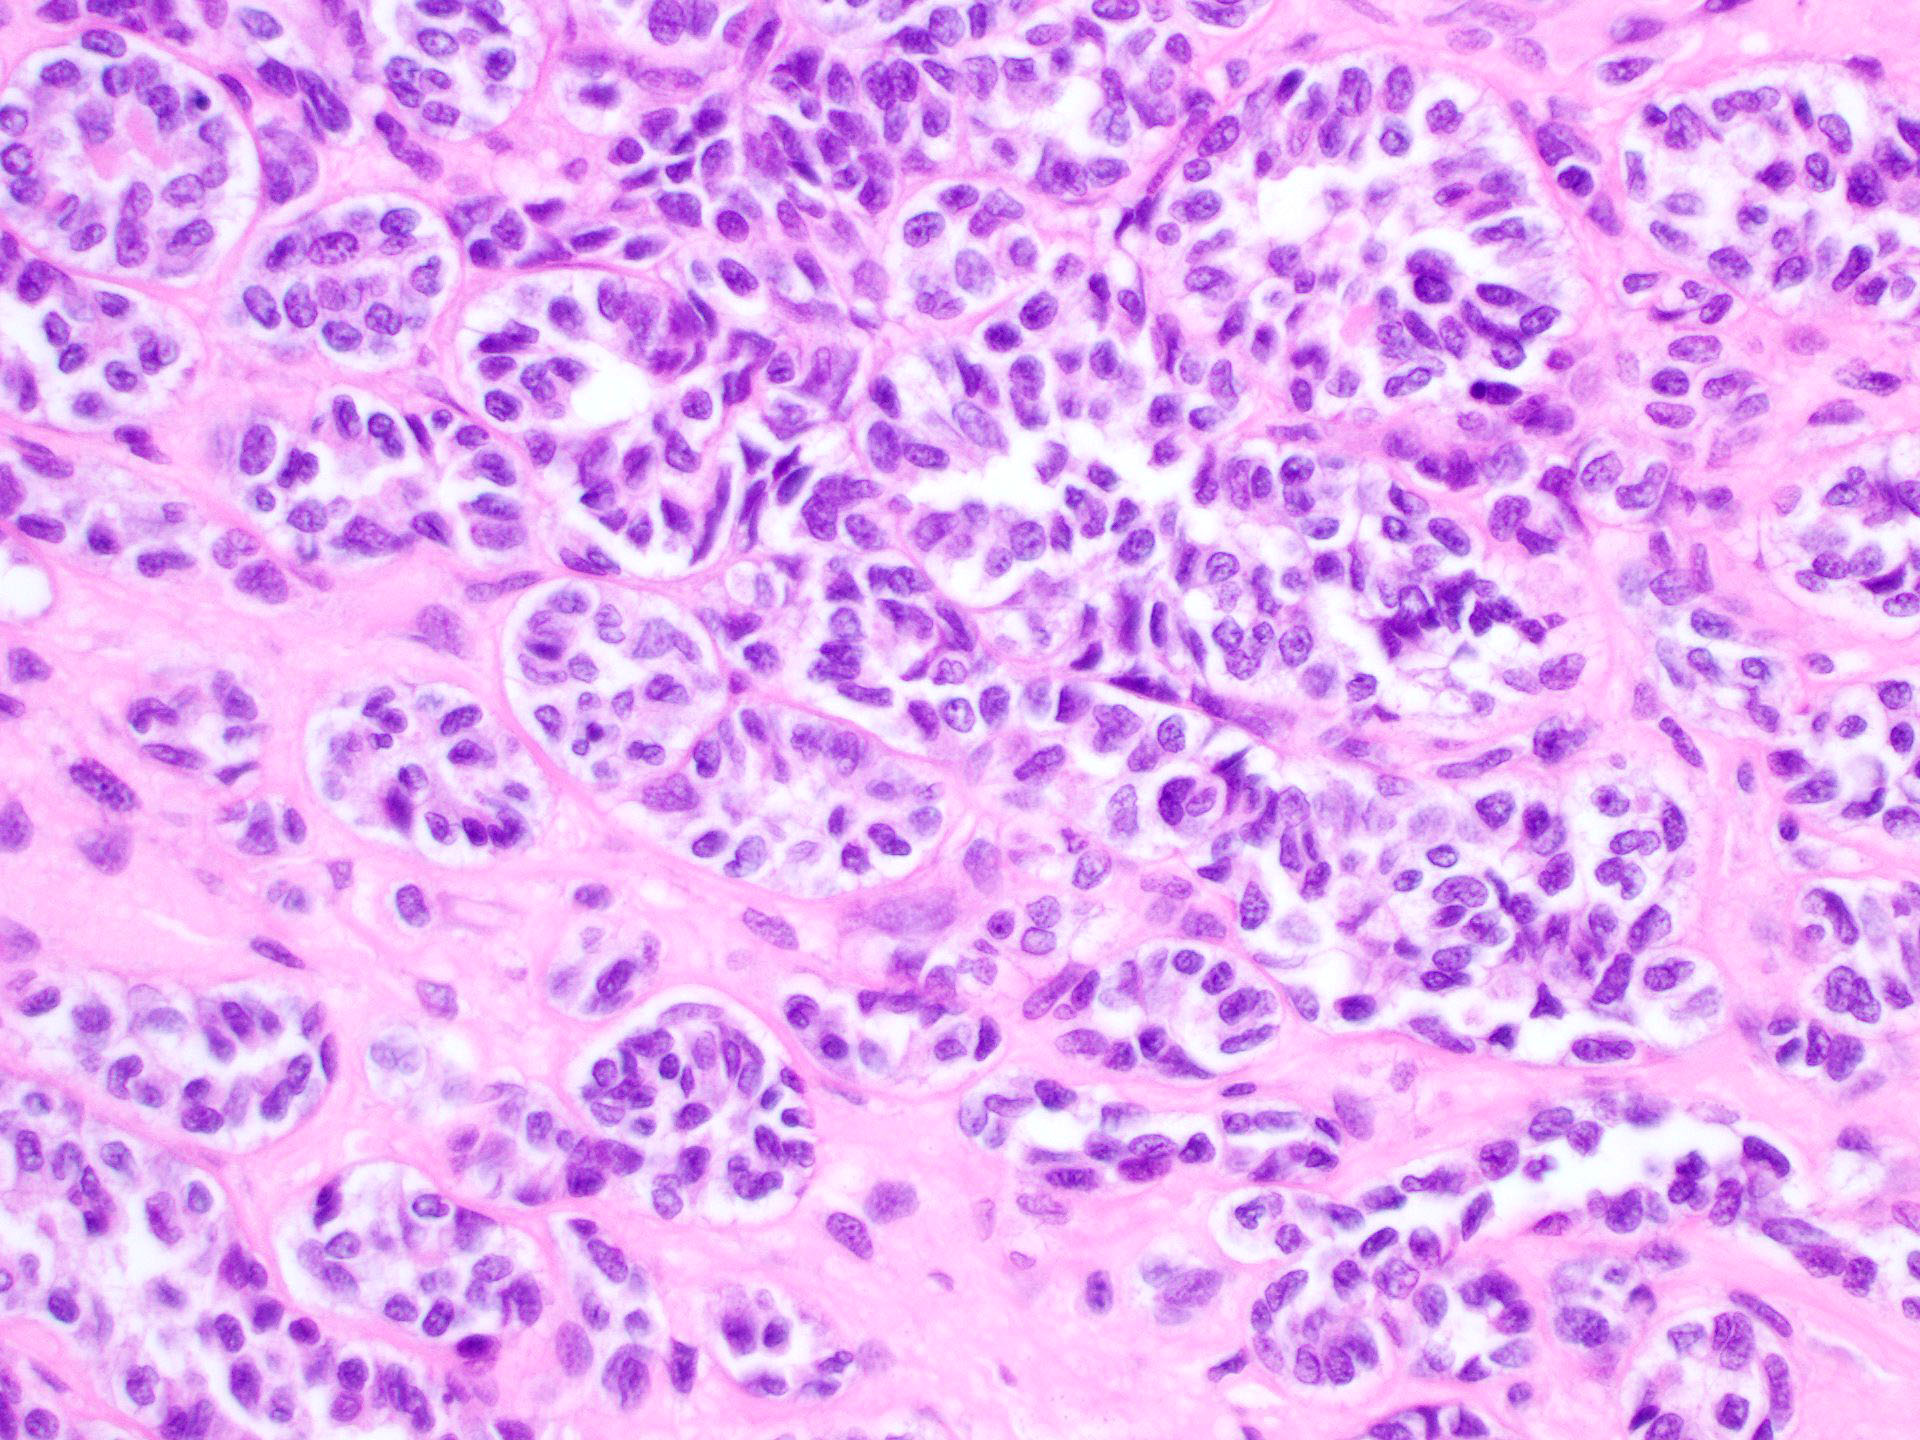

Microscopic (histologic) description

- Tubular pattern (most common and usually present at least focally) with solid or hollow tubules

- Cuboidal or columnar cells

- Bland oval to round, monotonous nuclei

- Pale cytoplasm

- Other patterns: trabecular, diffuse, alveolar, pseudopapillary, reniform, pseudoendometrioid, spindled

- Absent to very rare Leydig cells

- Pathologic features predictive of malignant behavior include 5 mitoses per 10 high power fields, severe cytologic atypia, necrosis and size > 5 cm